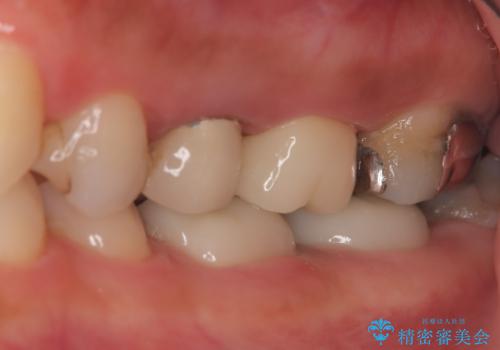

左上第一小臼歯のインプラント治療

- 患者様は、左上第一小臼歯の垂直性歯根破折が確認され、抜歯が必要となりました。本来、抜歯即時埋入を適用できるケースでしたが、患者様のご都合によりブリッジとインプラントで一度悩まれるとのことで待時埋入となりました。治療計画では、上顎の骨の状態を慎重に評価し、デンサーバーを用いてドリリングを行うことで、上顎洞粘膜を傷つけずにインプラントを埋入する方法を選択しました。埋入後の安定を確保するため、術後の経過観察を慎重に行います。

待時埋入では、抜歯後に骨の再生を待つ必要があり、即時埋入に比べて治療期間が長くなります。しかし、デンサーバーを使用した精密なドリリングによって、上顎洞粘膜を破らずにインプラントを埋入することができ、術後の合併症リスクを最小限に抑えることができました。インプラント埋入後は、骨との結合を待ちながらしっかりとしたケアと定期的な検診を行い、最終的な補綴物の装着に備えます。